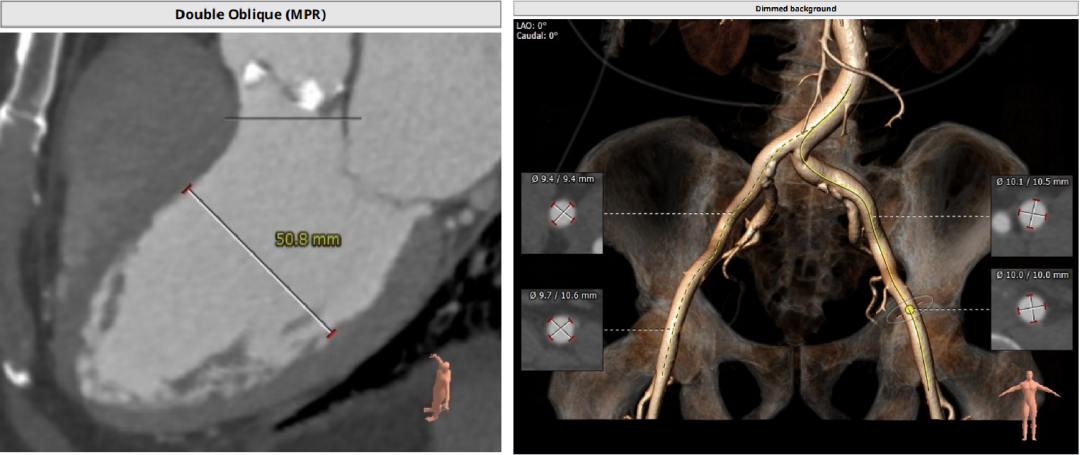

CT分析

以3个窦消失最低点确认的平面作为虚拟瓣环平面初步筛选瓣膜尺寸。自展瓣参考周长得出的Annulus直径,该病人为25.8,根据自膨胀瓣膜特点需要oversize,初步判断为29/32瓣膜。LVOT直径大于Annulus,短径24mm,足够限制瓣膜,提供锚定支撑力。STJ高度足够,可提供足够空间给原有瓣叶,过宽的STJ则无法提供释放中锚定支撑力。

窦部的空间与左右冠脉开口高度结合瓣叶形态,是否增厚可以初步判断瓣叶是否会在瓣膜植入后遮挡冠脉开口造成急性的冠脉堵塞。该病人左冠开口略低,且钙化集中在右冠和无冠窦,判断冠脉风险较高。需术中球扩判断是否进行冠脉保护。

升主动脉未见增宽,心脏角度合适极重度钙化,多集中在基底部位二叶瓣重度钙化THV需要downsize选择26/29瓣膜。

入路:入路观察是否有溃疡、钙化、迂曲、血管狭窄等情况,以判断夹层风险。该病人入路情况良好,优先选择右股作为输送系统主入路。